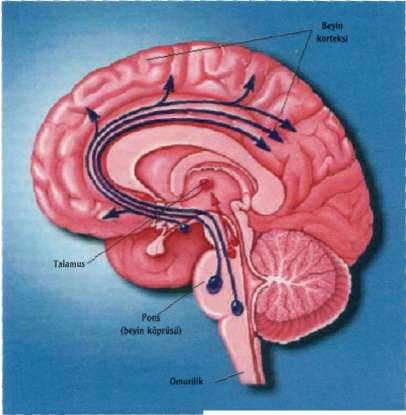

Uykunun Denetimi

Uyanık kalmak beyindeki iki farklı sistemin salgıladığı mesajcı moleküllere bağlı. Uyanık kal­mayı sağlayan ilk sistem, "asetiikolin" adlı bir mesajcı molekülün, beynin alt kesimlerin­de bulunan talamusu uyarmalıyla işlevini yürütüyor. Uyarılan talamus, korteks de­nen beynin dış kabuğuna, yani bilinç düze­yine uyarılar yolluyor. Bu uyarılar sayesin­de beyin dalgaları değişerek uyanıklık du­rumundaki dalgalar oluşuyor. Uyanık kal­mamızı sağlayan bu sisteme "kırmızı yol" deniliyor. Uyanık kalmamızı sağlayan di­ğer sistemse "mavi yol". Bu sistemde, no-radrenalin ve serotonin gibi mesajcı mole­küller beyin korteksini uyarıyor. Bu uyarı­lar bilinçli kalmamızı sağlıyor. Uyanıkken bu moleküller sürekli salgılanarak beyne uyarı gidiyor. Uykunun yavaş dalga evre­sinde her iki sistem yavaşlıyor ve bu me­sajcı molekülleri salgılayan nöronların ateşlemesi duruyor, REM uykusu sırasın-daysa asetilkolin uyarısı devam ediyor an­cak noradrenalin ve serotonin ateşlemesi tümüyle kesiliyor. Uykuyu kontrol eden di­ğer bir merkezse "hipotalamus". Bu böl­gede bulunan iki grup nöronun salgıladığı mesajcı moleküller uykuya dalmamızı de­netliyor. Buradan salgılanan "CABA" adlı mesajcı, uyanık kalmamızı sağlayan mer-

kezleri baskılayarak uykumuzu getiriyor. Bu böl­gede meydana gelen bir hasar, uykusuzluğa yol açıyor. Hipotalamusun yan tarafında bulunan